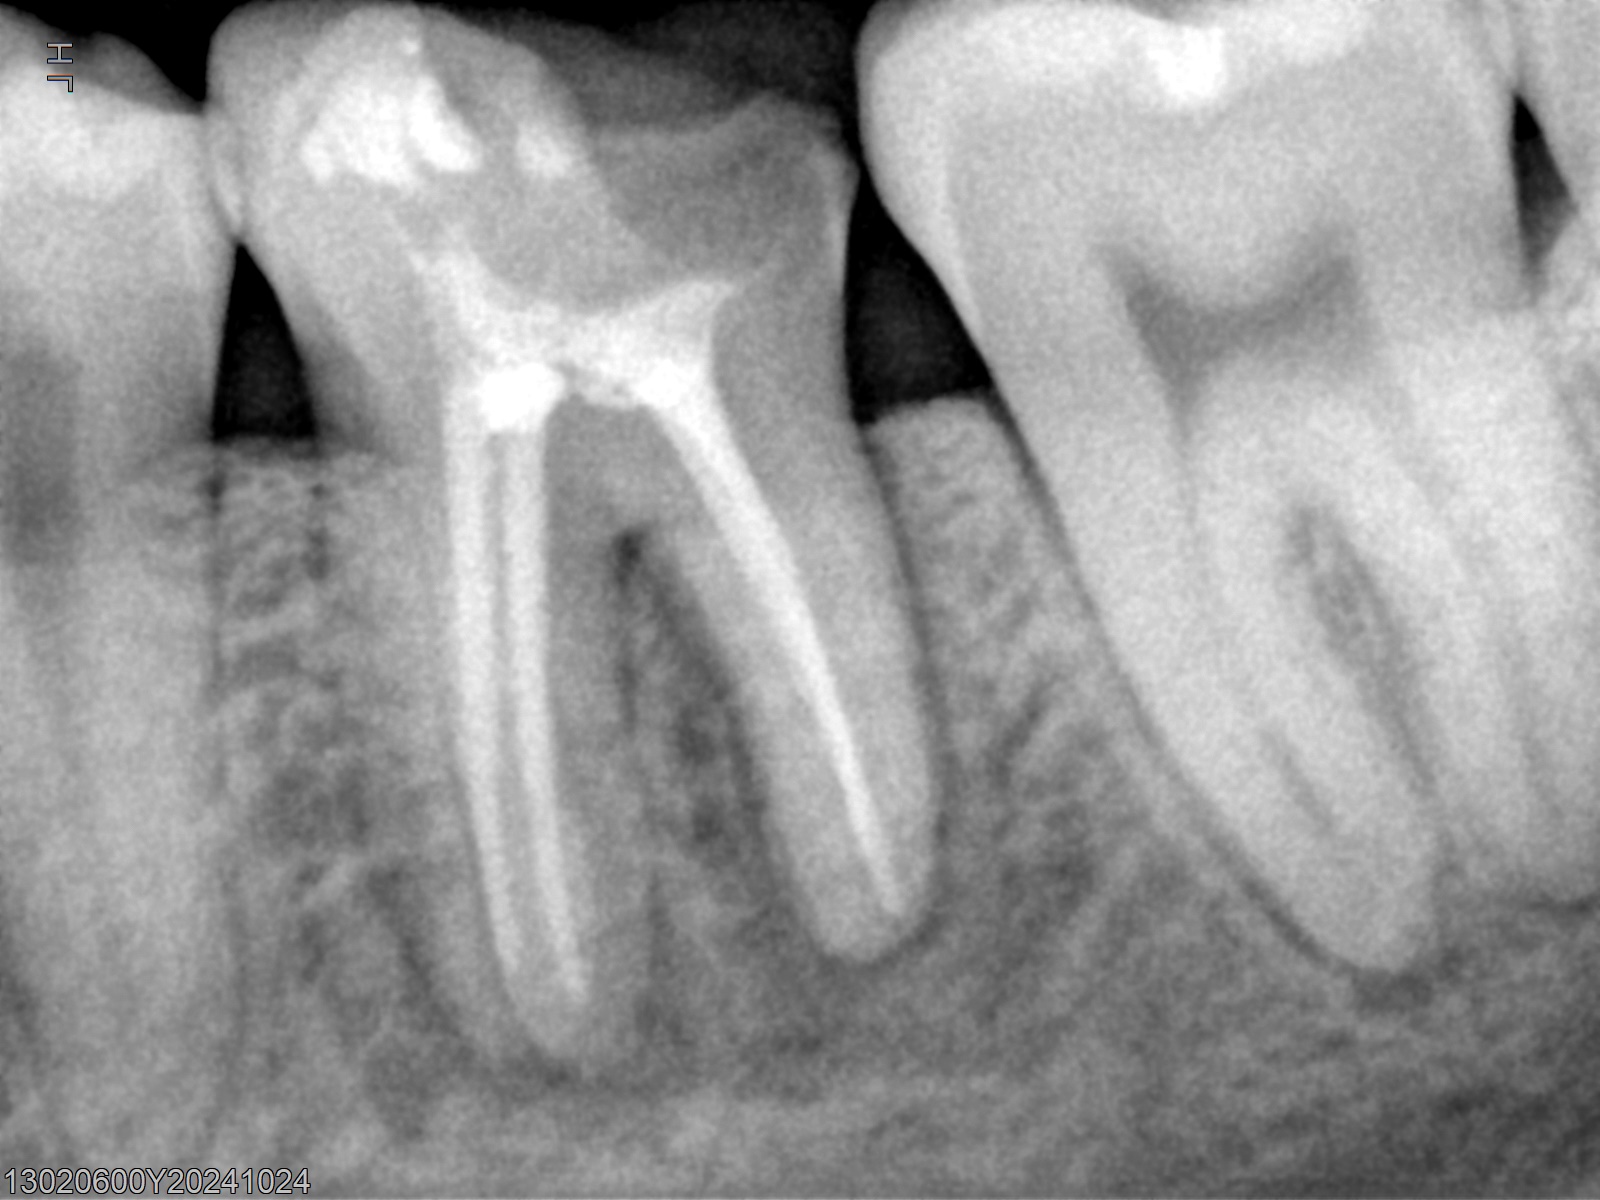

Veja alguns casos de sucesso